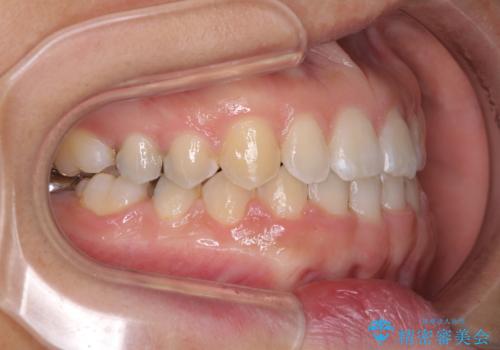

元々の歯並びが悪くなかったため、9ヶ月で綺麗に仕上がりました。

すきっ歯は後戻りを起こしやすいため、上下ともに歯の裏側を細いワイヤーで固定した上で、リテーナーのマウスピースを装着していただいています。